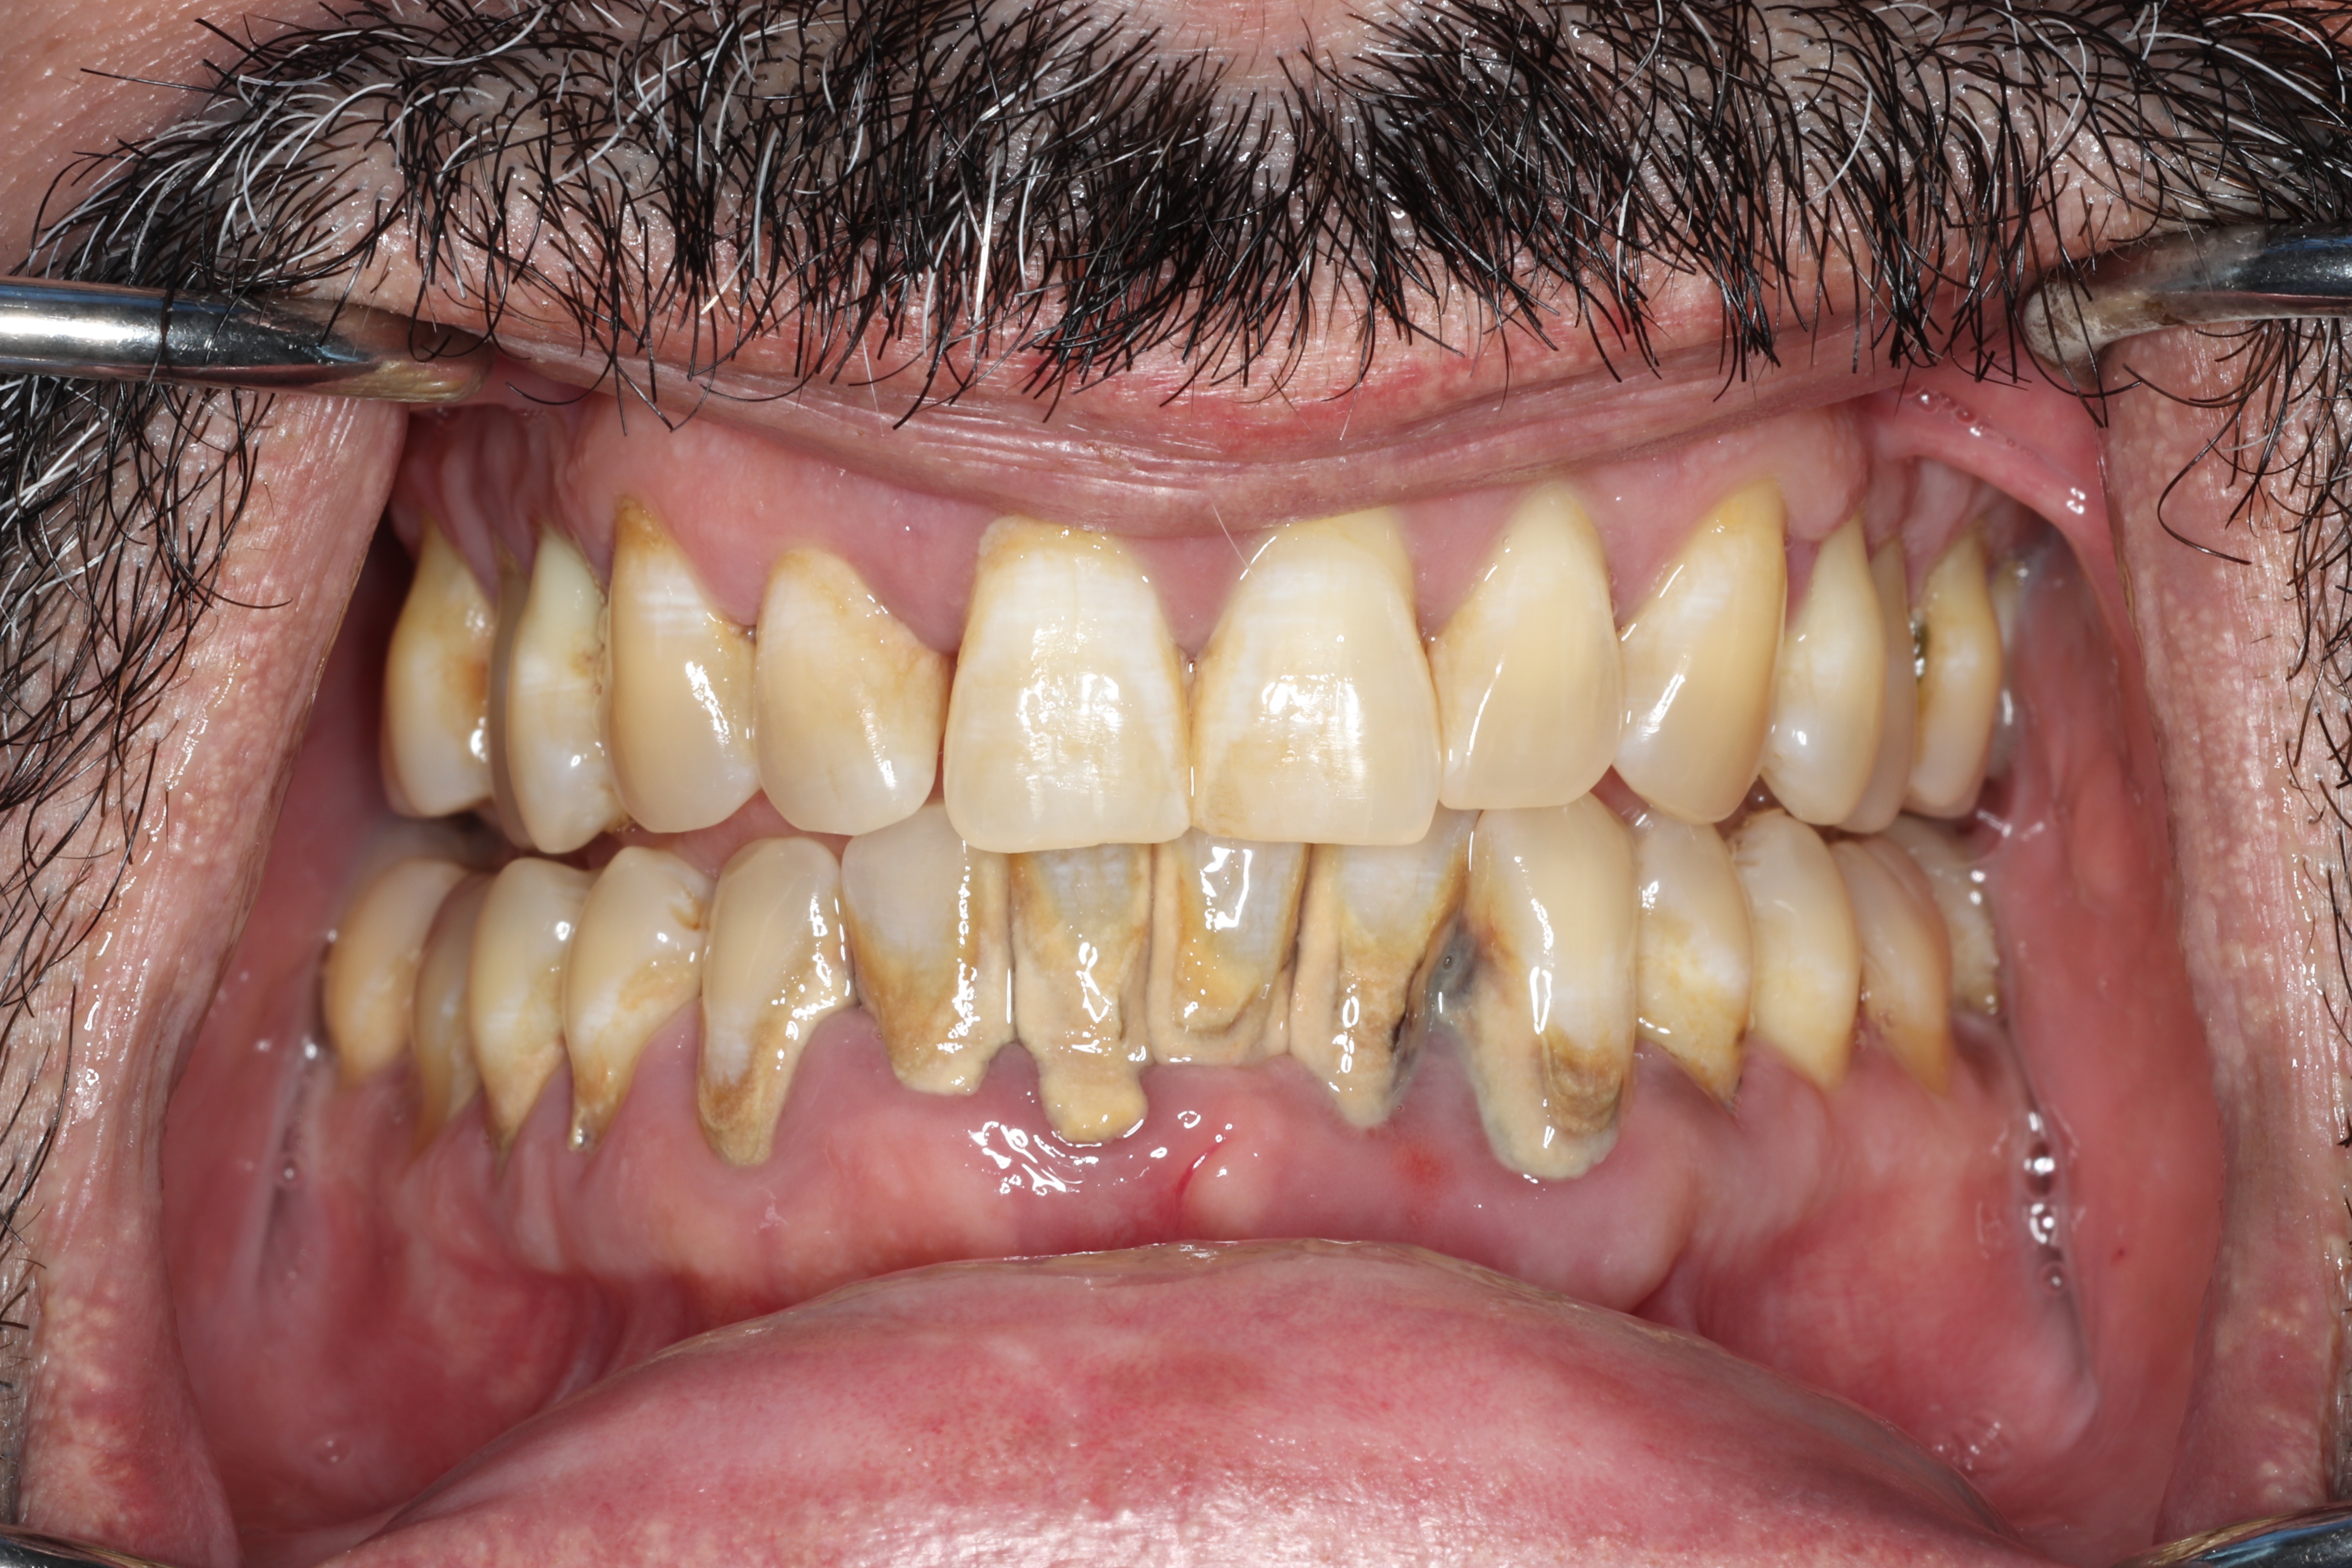

As bone is lost, you may notice teeth feeling looser, teeth shifting position, gaps developing where teeth used to be tight together, food getting stuck in new places, difficulty chewing, and increased sensitivity as root surfaces become exposed. Gum recession can change the appearance of your smile. In advanced cases, painful infections (periodontal abscesses) can develop within deep pockets. Without treatment, the end result is tooth loss.

Effects on Your Daily Life and Confidence

Many patients report feeling self-conscious about their smile, worried about bad breath, embarrassed eating in public, or reluctant to speak closely with others. These feelings are entirely understandable and very common. The psychological stress can actually worsen the disease by suppressing your immune system, creating a cycle that treatment can help break.

Common signs include gums that bleed when you brush or floss, gums that are red or swollen, persistent bad breath, gums pulling away from your teeth, and teeth that feel loose. If you are experiencing any of these symptoms, ask your dentist to evaluate you for periodontal disease.